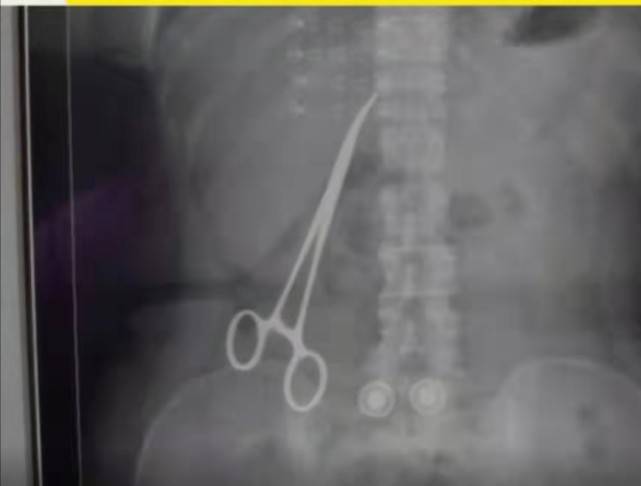

一把15厘米的止血钳 , 一台手术之后竟然遗留腹中 , 超过15个月 。

两个月后 , 疼痛难忍的祝女士来到禹州市中医院进行检查 , 结果显示 , 她的肚子里竟然“藏”了一把长达15厘米的止血钳 。

根据祝女士的说法 , 10年来 , 她总共只做过3次手术 。 第一次是10年前在郑州一家医院做的胃部手术 , 第二次是6年前在平顶山鲁山县医院做的剖宫产手术 , 第三次就是2020年6月 , 她在禹州市妇幼保健院做的二胎剖宫产手术 。

祝女士回忆 , 前两次手术后 , 她都没有出现身体异样 , 疼痛就是在禹州市妇幼保健院做完二胎剖腹产手术后才出现 。